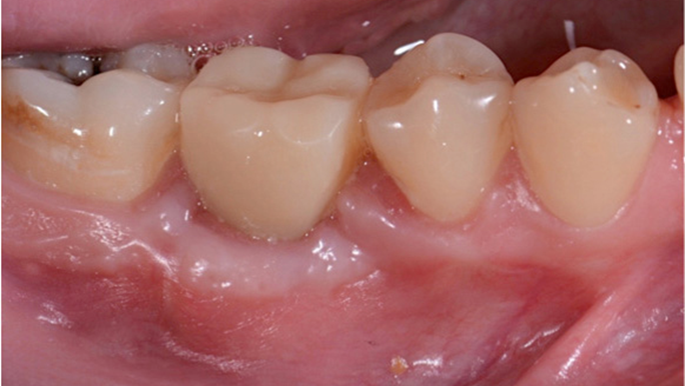

Clinical case: # 46 implant placement & GBR using i-Gen membrane for significant vertical resorption & mixed bone defect

- Courtesy of Dr. Iulian Filipov, Romania -